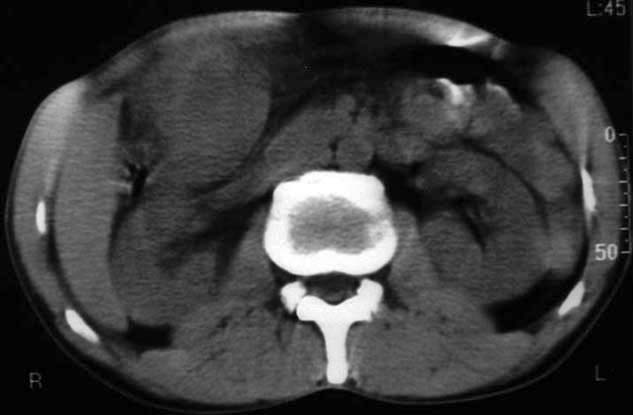

男,50y,右上腹包块痛10天,查:右上腹饱满,右肋下触及6*6cm大小包块,质硬,压痛。患者诉:10天前感冒胸闷,痛,后痛及右上腹部,既往有肝炎病史。

没有增强!只能考虑左叶内侧段巨块型肝癌(外生型)可能性大;胆囊呢?不除外胆囊癌累及肝脏。

病变位于胆囊窝内,其内密度不均,肝总管及胆总管扩张,胃里面没有清水充盈,不解为什么楼主不做好了准备再做呢,支持:“左叶内侧段巨块型肝癌(外生型)可能性大;不除外胆囊癌累及肝脏”建议增强吧。

考虑:肝左内叶巨块型癌,主动脉旁淋巴结转移.(有一层面似见胆囊受压.)